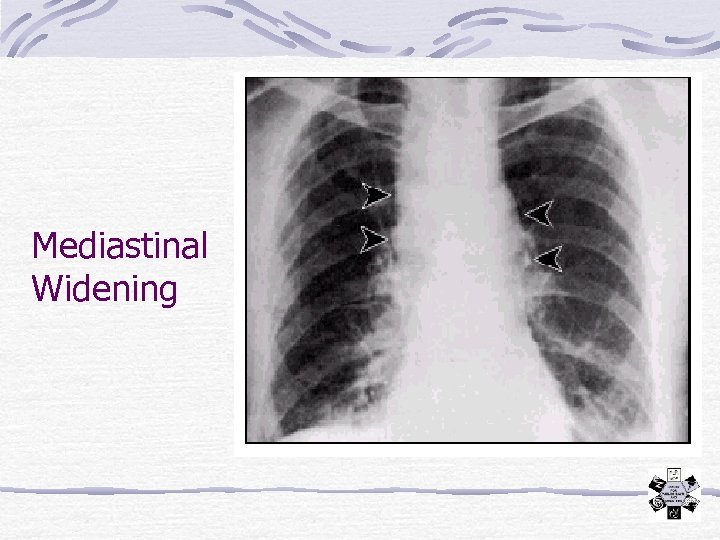

Mediastinal Widening

Case 1 - Dyspnea, Hypotension Patient admitted to ICU: Fluids, Intubation, Ceftriaxone, Vanco. , Gent. Later the same day a similar patient presents Also a stock trader in the same building Both patients deteriorate and die the next day